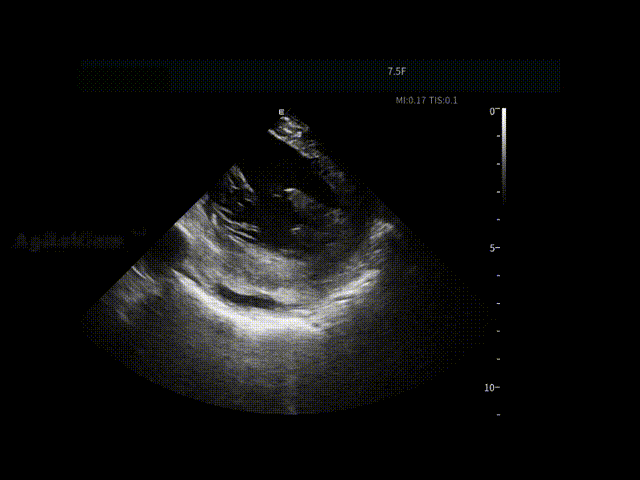

消融手术启动后,AgileView™ ICE导管即作为术中影像工具先介入。通过导管的打弯与旋转,术者对左心房,左心耳及心包区域进行连续,系统的动态扫查,在消融前全面掌握关键解剖信息。

ICE实时超声影像帮助术者直观评估左心耳内是否存在血栓,并同步观察心包状态,为手术是否继续推进提供重要影像依据,使后续操作建立在"可视,可判断"的安全基础之上。

LAA血栓筛查

术前心包-有明显积液